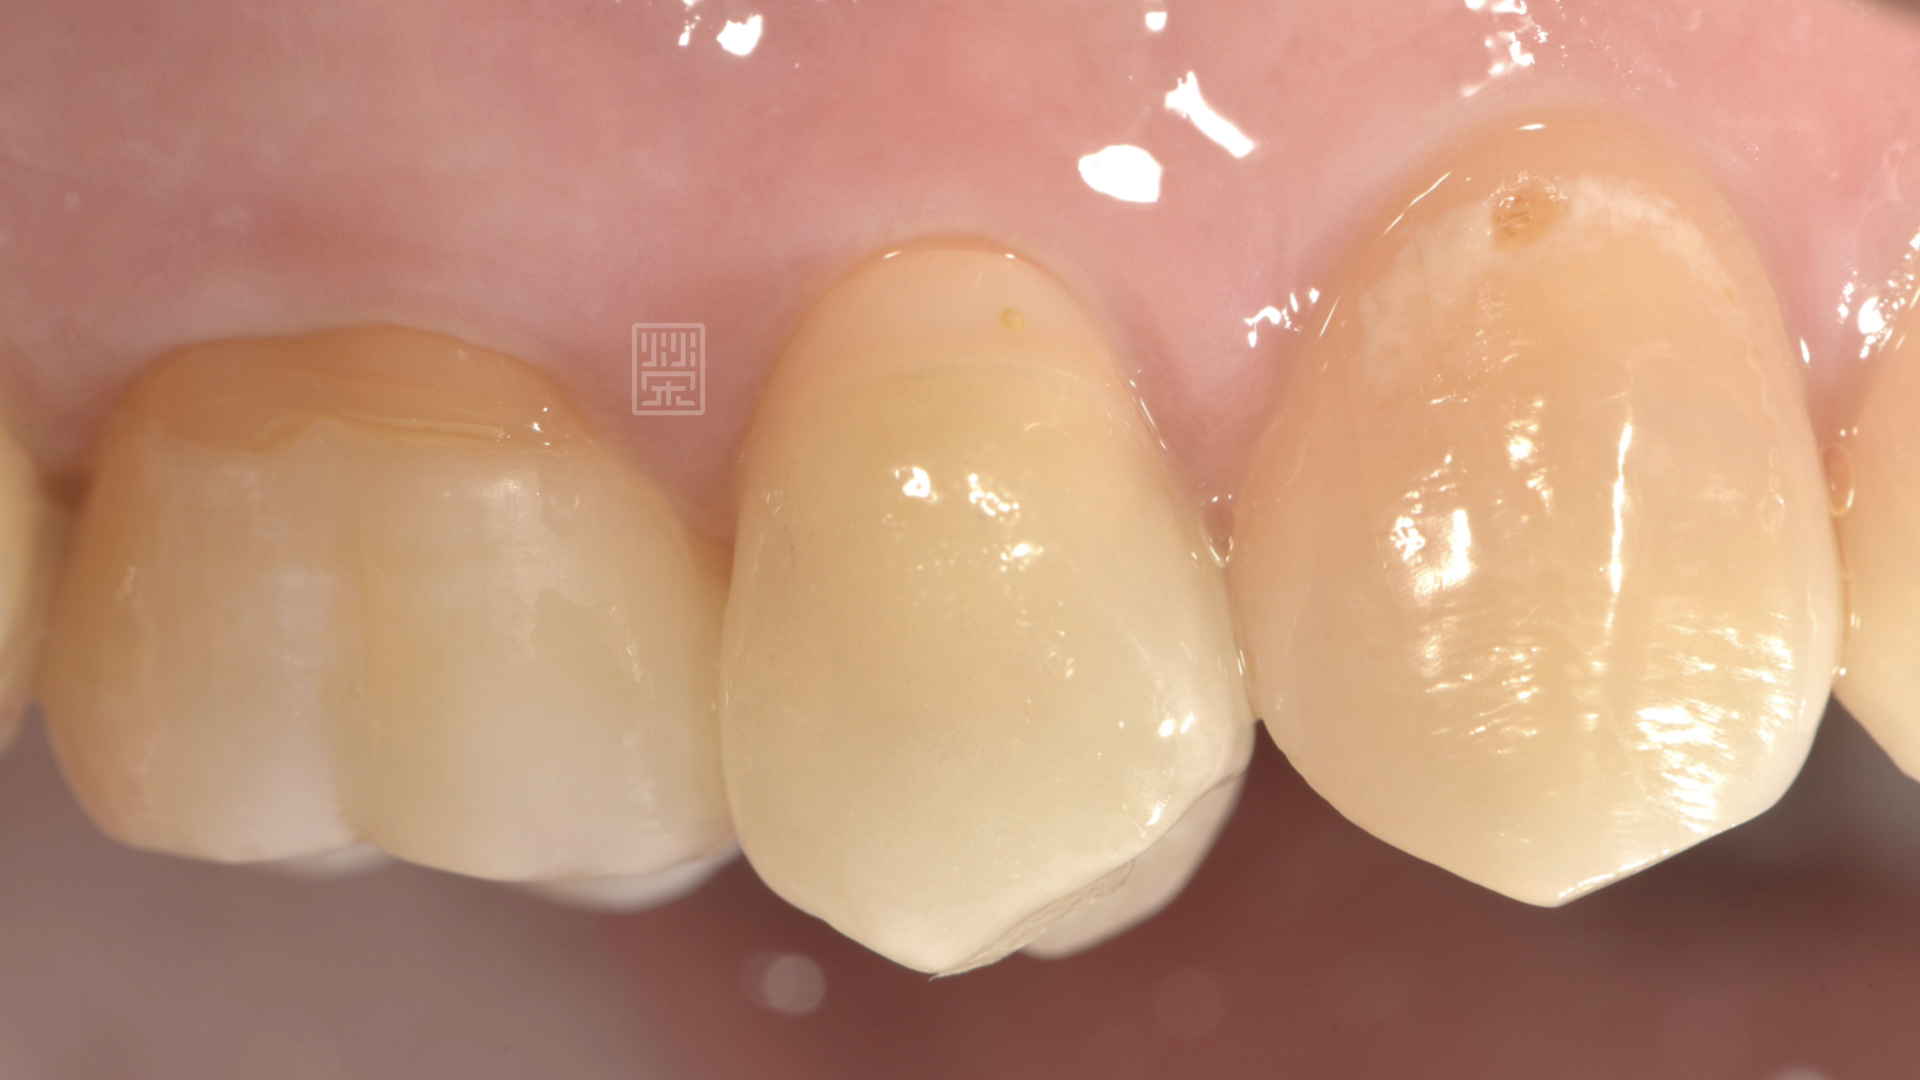

小臼齒齒縫間有個小洞,很容易塞食物

全瓷嵌體修復治療完成